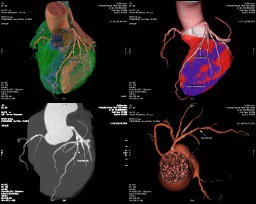

Bệnh nhân nam 66 tuổi, quốc tịch Nga đến Phòng khám Trái Tim Vàng vì tăng huyết áp mới xuất hiện. Kết quả MSCT động mạch vành cho thấy hẹp nặng 3 nhánh động mạch vành, vùng thiếu máu cơ tim diện rộng – dấu hiệu của bệnh mạch vành tiến triển.

Chụp MSCT động mạch vành – giúp xác định vị trí và mức độ hẹp chính xác nhất

Phòng khám Đa khoa Trái Tim Vàng được trang bị hệ thống MSCT động mạch vành hiện đại, đội ngũ bác sĩ tim mạch đầu ngành, giúp phát hiện sớm và điều trị hiệu quả bệnh mạch vành.